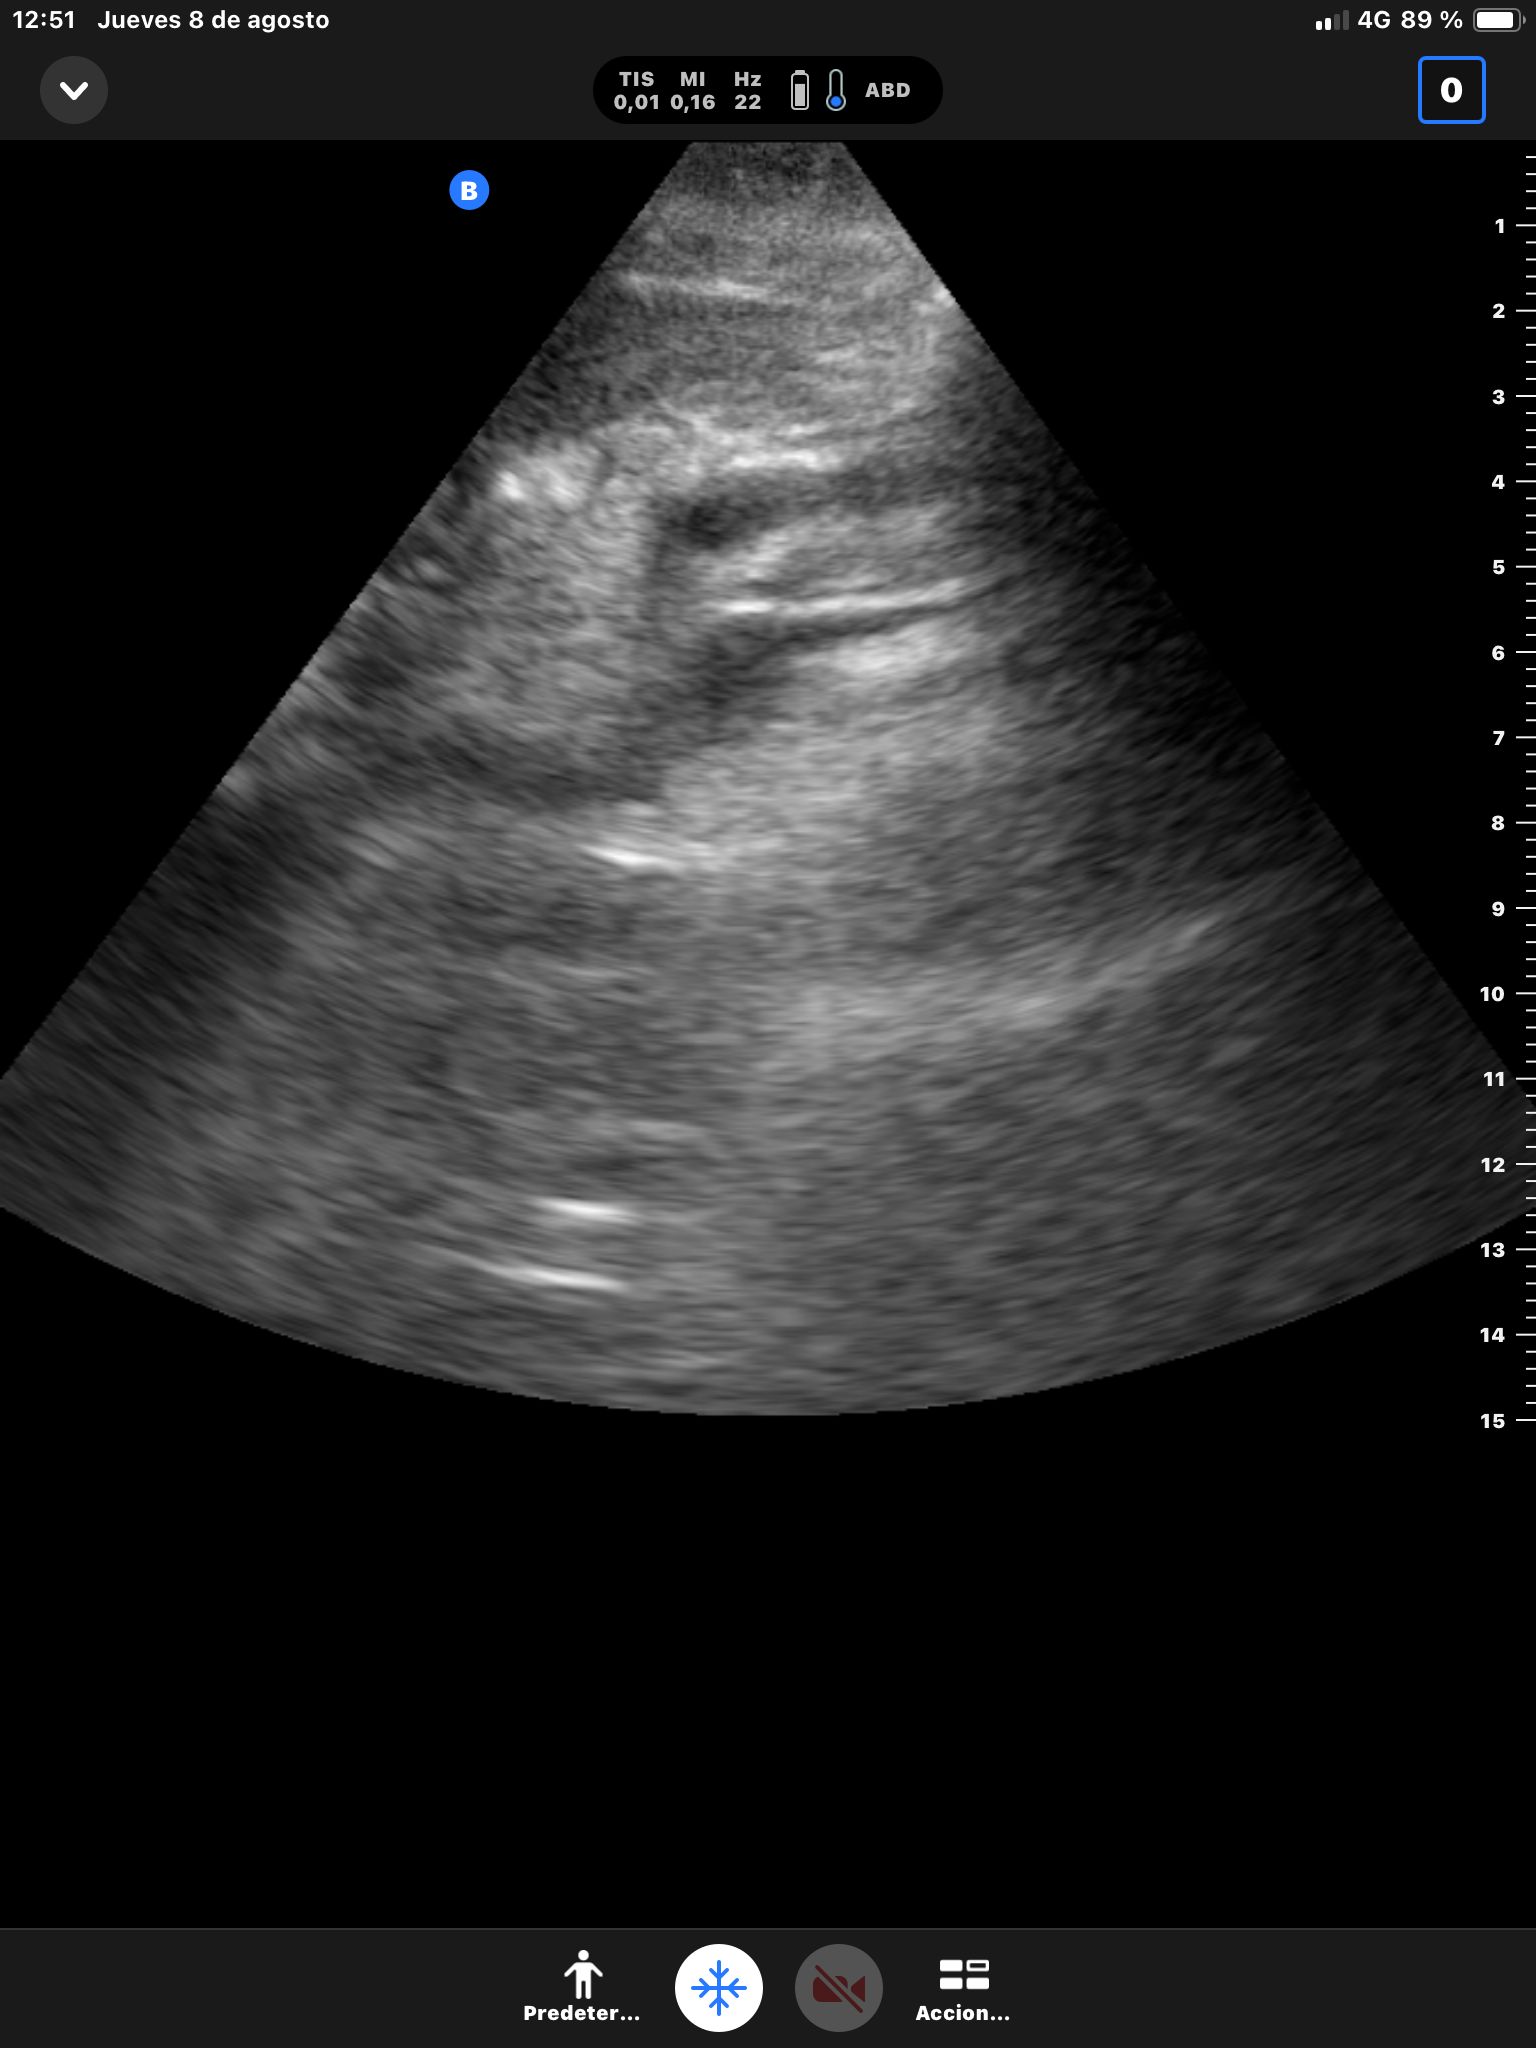

Se realiza ecografía abdominal.

Descripción de los hallazgos ecográficos y las imágenes más relevantes para la resolución del caso

Hígado sin LOEs. Vesícula biliar con hidrops (58 mm), dilatación del colédoco (10 mm). Páncreas hiperecogénico, atrófico, Wirsung de 76 mm.